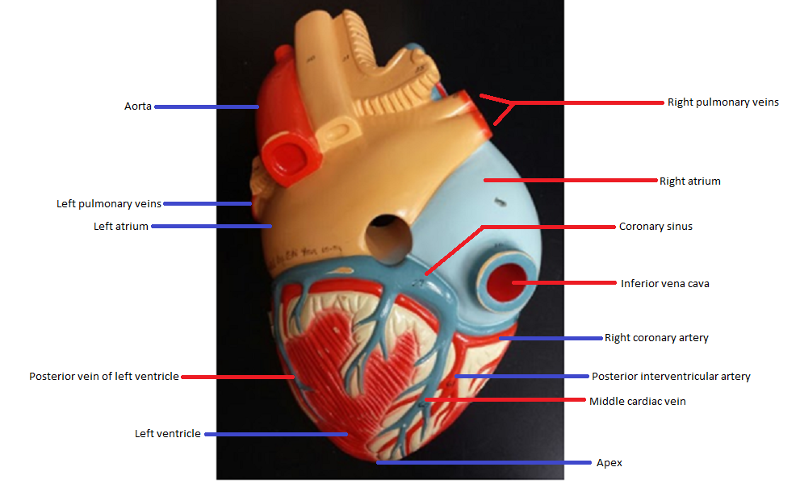

Name the missing parts.

Heart frontal section